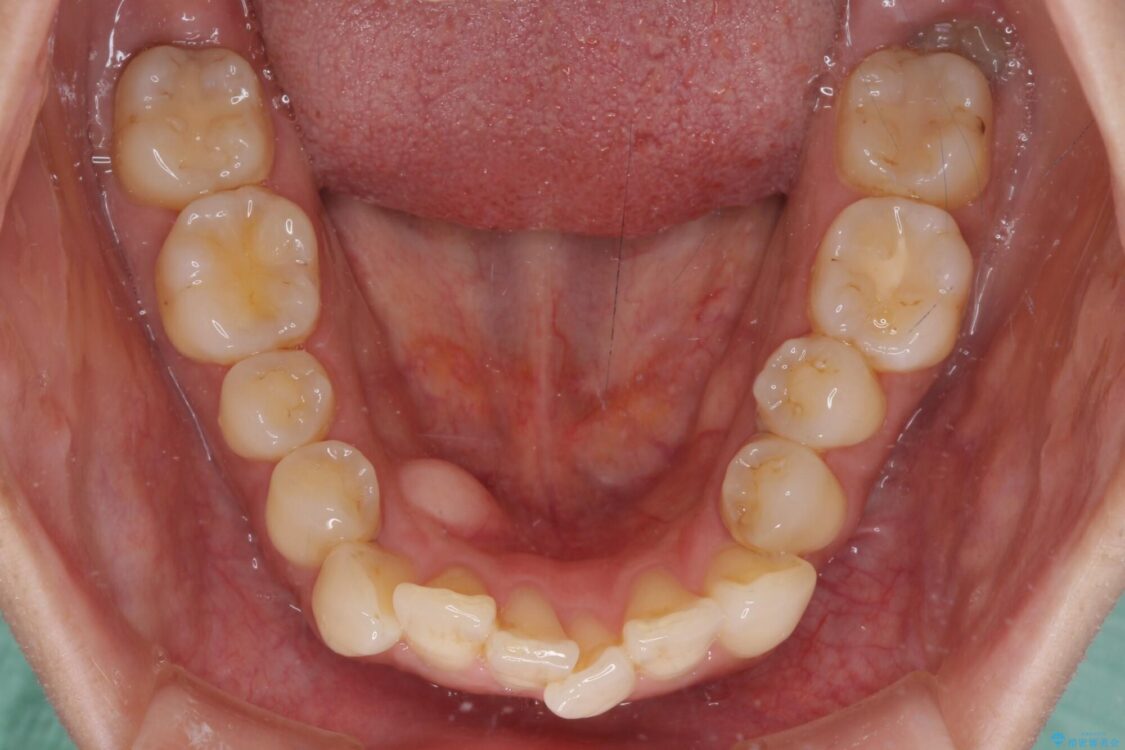

治療後について

歯の傾斜が改善され、インプラントによるクラウンが装着されたことで、物が挟まることもなくなりました。

治療後

• インビザラインによる矯正治療と奥歯のインプラント治療 治療後画像